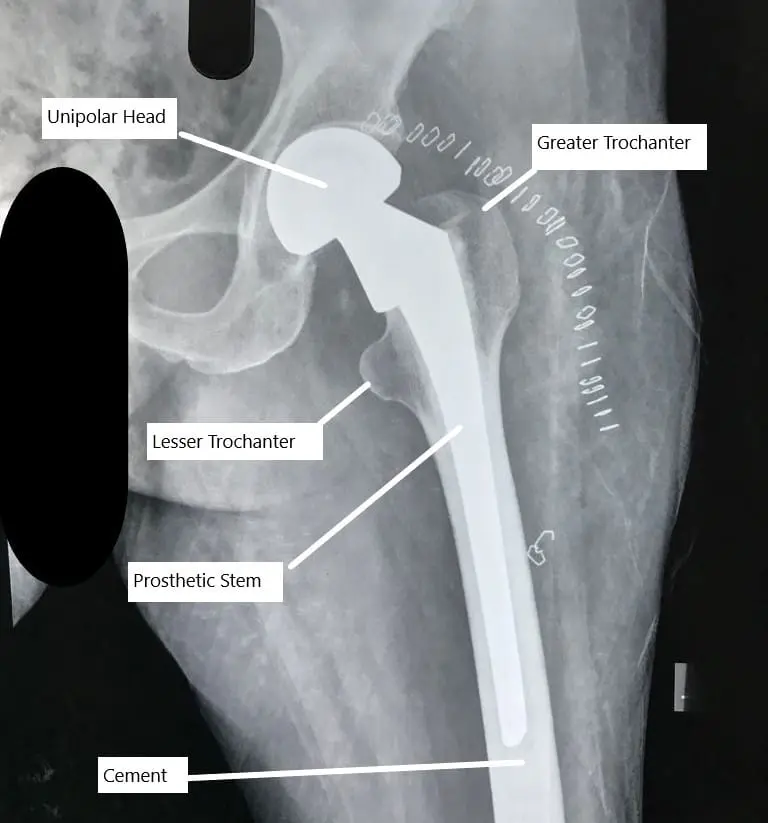

Partial unipolar hip replacement X -ray

Unipolar and bipolar are two types of partial hip replacement. The unipolar replacement is rarely performed and most of the partial hip replacement surgeries are bipolar. In a bipolar hip replacement, the prosthetic head of the femur actually consists of two balls. A smaller metallic ball rotates inside the larger metallic ball. A high grade polyethylene plastic covers the inner metal ball to provide a smooth rotating surface.

Compared to bipolar, a unipolar partial hip replacement only consists of a head firmly attached to the stem of the prosthesis. The bipolar design provides greater stability, movement and also helps protect the articular cartilage. The ball in ball design mimics the socket of the total hip replacement.